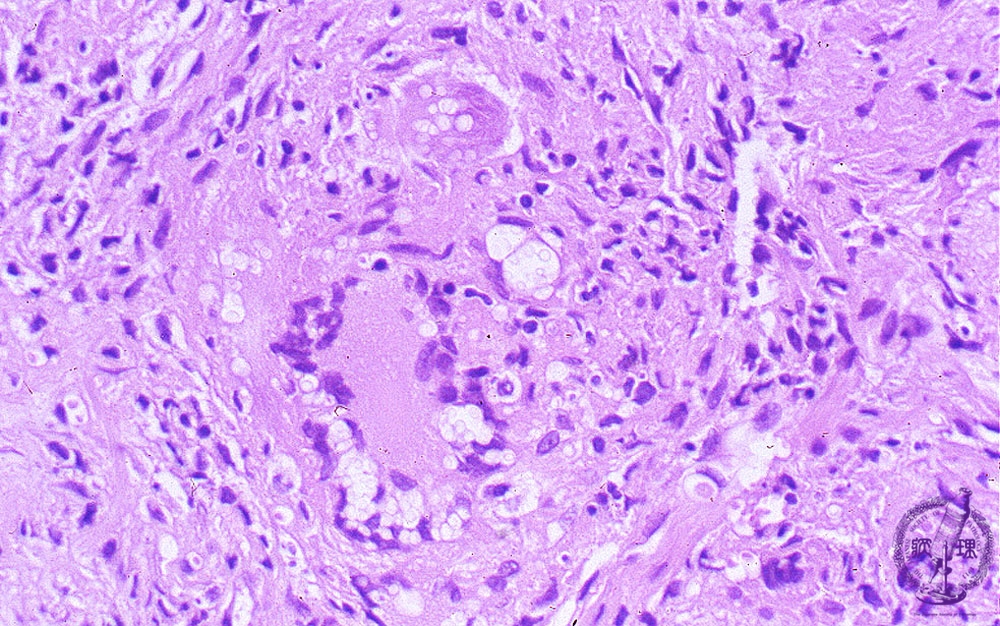

- ★(9)Fungal pneumonia (Cryptococcosis)

Microscopic view (HE stain, high power view): Cryptococcosis is basically a granulomatous lesion. Cryptococci may only be identified as non-staining foci on HE because this stain does not highlight the organism.